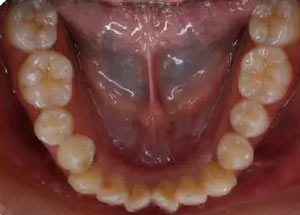

下牙弓:卵圓形,下前牙區(qū)擁擠

上牙弓擁擠度9mm;下牙弓擁擠度7mm;

………提示上牙弓較下牙弓狹窄

橫向:上下牙弓寬度不匹配,下牙弓寬度較上牙弓大,左側(cè)自第一磨牙開(kāi)始至側(cè)切牙均為反合。上牙列中線左偏,下牙列中線右偏。